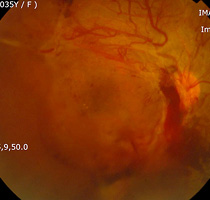

증식당뇨망막병증에서범망막레이저광응고술

증식당뇨망막병증에서

섬유혈관증식과 견인망막박리

유리체절제술 후